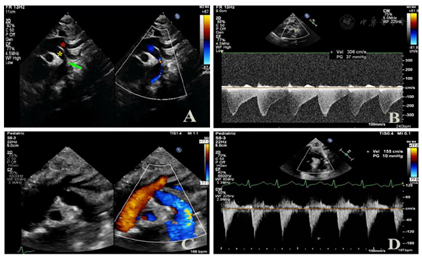

心电图提示:窦性心动过速;T波改变。床旁超声心动图:1.升主动脉于主动脉弓起始段(弓部内径约0.6cm)发出上位动脉弓和下位动脉弓两大分支,上位动脉弓分出头臂干、左颈总动脉、左锁骨下动脉后,多切面探查为盲端;下位动脉弓下行延续为降主动脉并降段狭窄,狭窄处内径约0.1cm,降主动脉起始段狭窄后扩张,内径约0.9cm。CDFI示降主动脉狭窄处血流速度增快,峰速3.1m/s,压差36mmHg(图1A、图1B);2.全心增大,左、右室室壁运动弥漫性减弱。另房间隔中部见一宽约0.66cm连续中断。二、三尖瓣形态、开放可,闭合不佳。CDFI:房间隔连续中断处见左向右为主的双向分流信号;降主动脉与左肺动脉见可见一细束左向右分流信号;二尖瓣口收缩期左房侧见中量反流信号;三尖瓣口收缩期右房侧见中至大量反流信号(图2A、图2B)。超声心动图显像提示:复杂先天性心脏病:1.主动脉弓发育异常永存第五主动脉弓(B型)并降主动脉缩窄;2.第四主动脉弓离断;3.房间隔缺损(左向右为主的双向分流);4.动脉导管未闭(即将闭合);5.二尖瓣中度关闭不全三尖瓣中至重度关闭不全;6.全心增大左、右室收缩功能测值减低;7.重度肺高压。